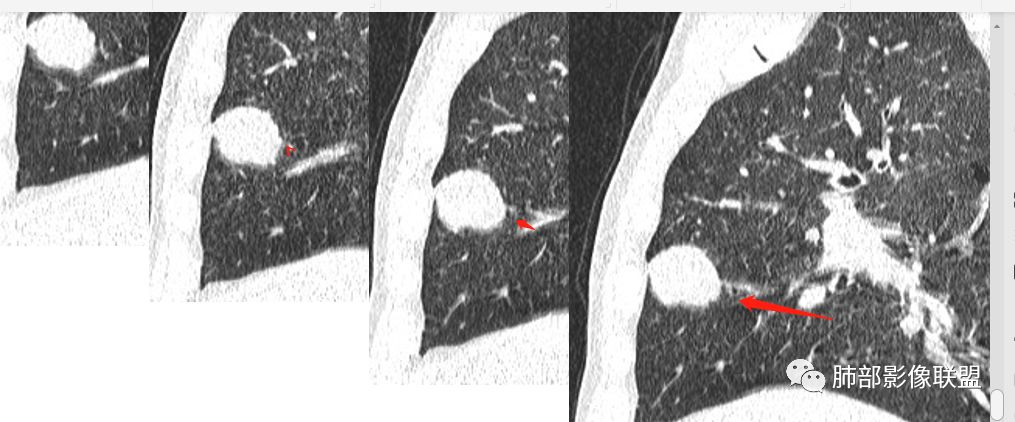

目测这里还是有强化,其余地方强化幅度不是很明显

浅分叶

边缘膨隆

常规会考虑恶性

细胞类型我觉得还是让病理去定吧

薇:各位老师,下面是该病例的横断位薄层

3.外侧可见血管进入,病灶局部轻度强化。